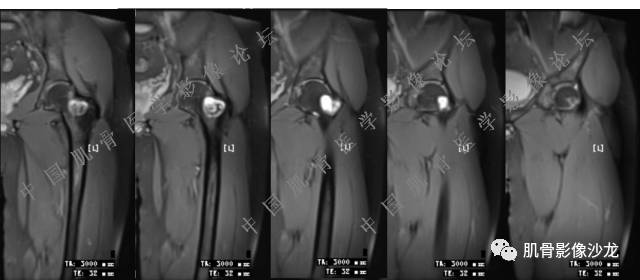

主诉:右大腿疼痛、活动受限20天

现病史:患者于20天前无明显诱因出现右下肢疼痛,活动受限,疼痛呈阵发性,活动后加重。自行口服止痛药芬必得,效果不佳,至当地医院治疗,检查发现右侧股骨近端病变。遂来诊

葛英霖 20:30 原发或继发动脉瘤样骨囊肿,继发于巨细胞瘤,软骨母,纤维组织细胞瘤,骨母等等

向以四 20:30 软骨母合并ABC,

医影在线 20:30 软骨母,/继发ABC

飞鹰行动 20:31 T2信号高,有软骨成分

Echo 20:32 T2确实有一块区域很亮 ,并有野液平

飞鹰行动 20:33 有侵袭性

飞鹰行动 20:35 骨皮质破坏,周围骨质异常信号

葛英霖 20:36 这不是良性病变

葛英霖 20:36 中间型可能性极大

葛英霖 20:37 明显侵蚀骨内膜啊,硬化边也不完整 (细箭头所示)

葛英霖 20:43 提不提也很明显继发了abc

葛英霖 20:44 是

葛英霖 20:46 明显的多囊状改变,液液平面